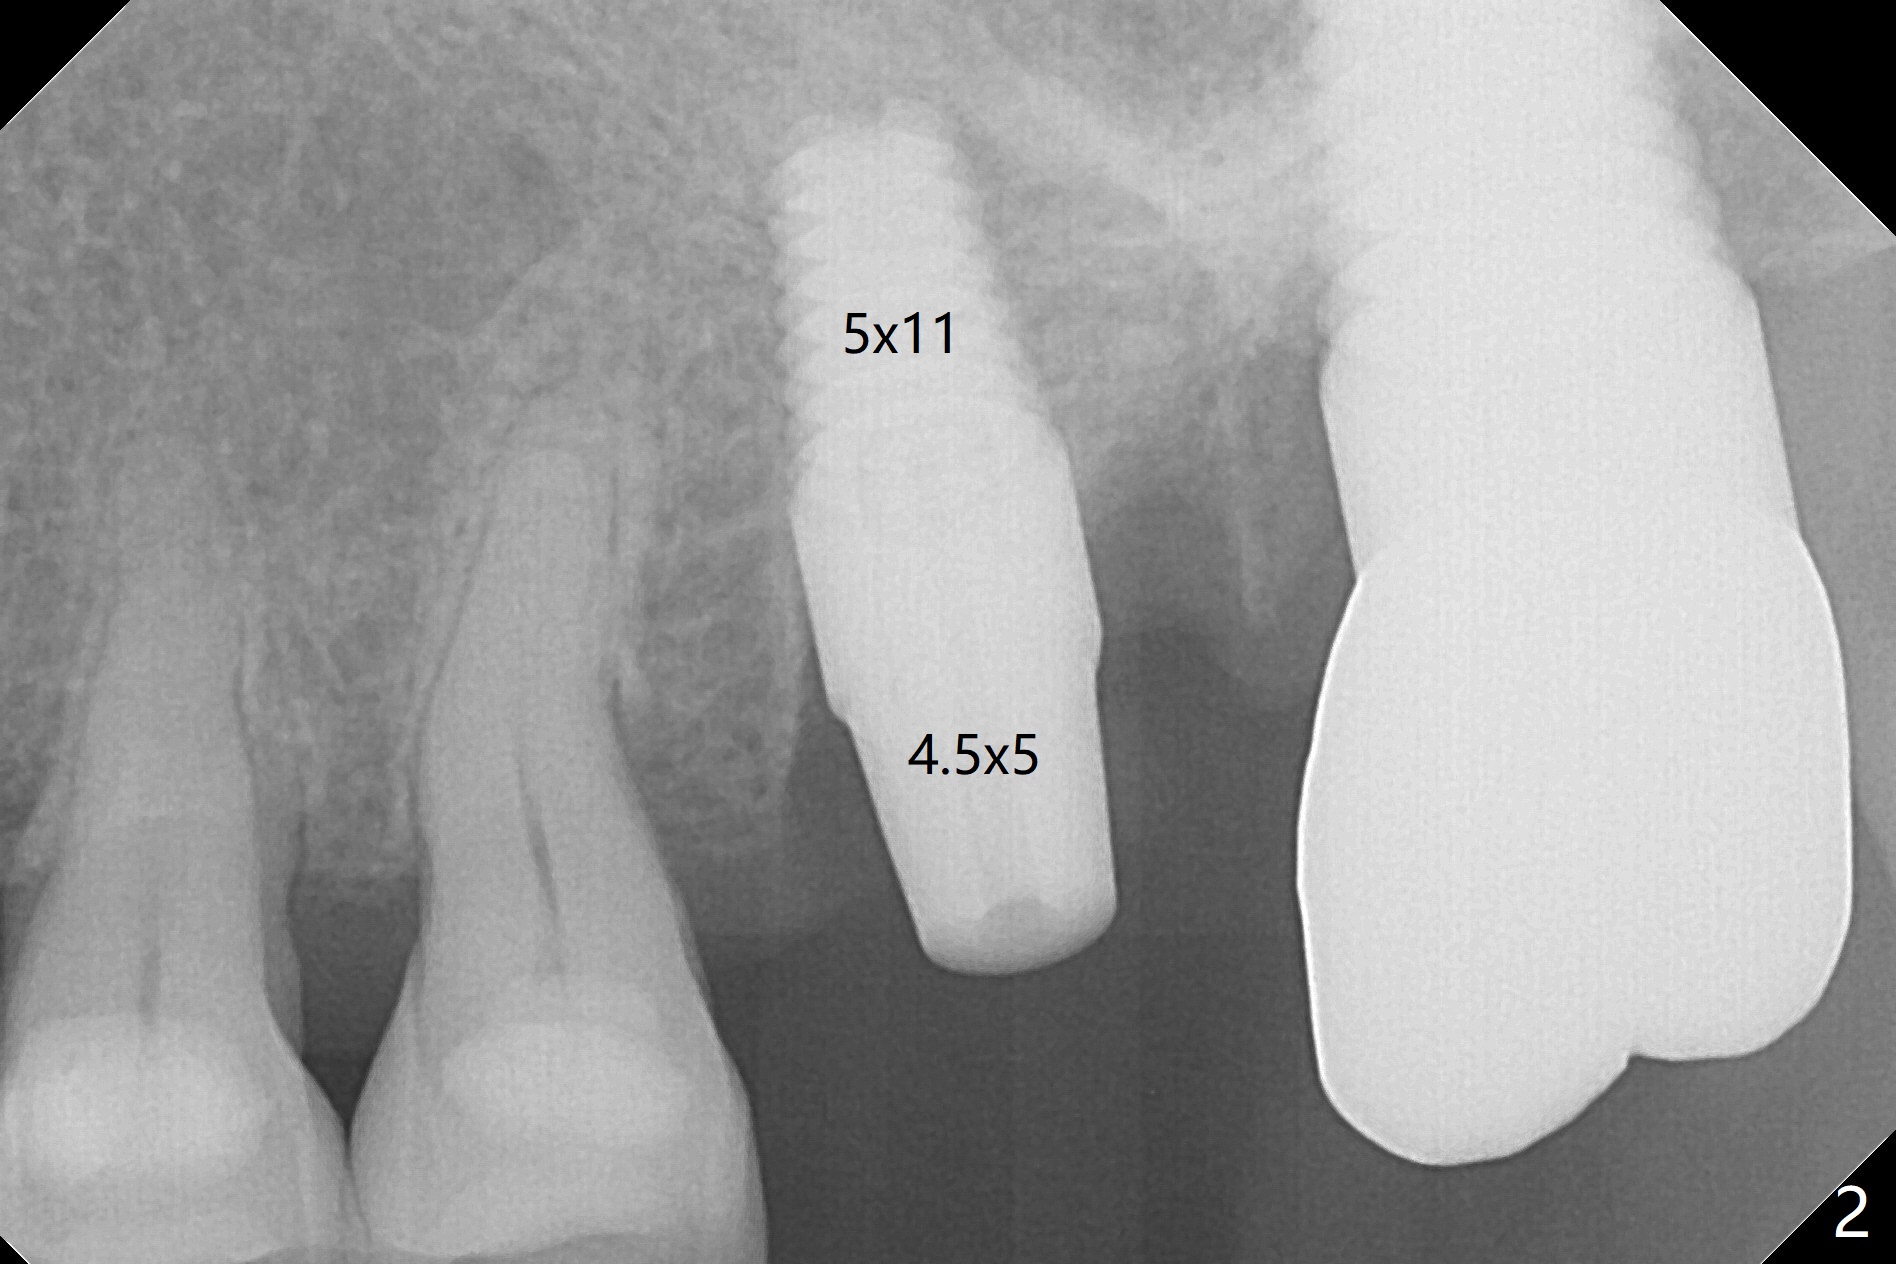

After osteotomy with guide at #14 (4.5x7.3 mm last drill with 1 O-ring/10.5 mm offset for bone-level implant), a 5x11 mm tissue-level tap is used with allograft for sinus lift (Fig.1). With one more round of allograft for sinus lift, a 5x11 mm tissue-level implant is placed with ~ 50 Ncm (Fig.2). CBCT 3-D images (Fig.3 (palatal view), 4 (distal view) (D: distal)) and coronal section (Fig.5 (P: palatal)) show the bone graft in the sinus (*). The patient returns for restoration 5 months postop in spite of running out insurance benefits because of discomfort with the immediate provisional. When the latter is removed (Fig.6), the gingiva is erythematous. It appears that the implant was placed deep. The abutment is removed for easy local oral hygiene. A healing cuff will be used or the implant will be reversely torqued. If the former is placed, a 4 mm longer abutment (4.5x9 mm) should be used to increase crown retention using temp bond . In fact the provisional forms a nice gingival cuff before cementation (Fig.7,8). Return to Upper Molar Immediate Implant, Prevent Molar Periimplantitis (Protocols, Table), Trajectory 18 Xin Wei, DDS, PhD, MS 1st edition 04/22/2019, last revision 02/28/2020